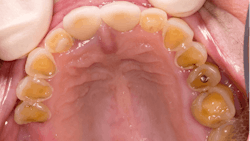

Dental erosion is a chemical process characterized by acid dissolution of dental hard tissue resulting in an irreversible loss of tooth structure. Acid destruction of the dentition occurs with both extrinsic and intrinsic factors. Extrinsic factors are caused by bacteria that produce acidic byproducts in persons that have diets high in sucrose and poor oral hygiene, or diets that are high in acidity. Intrinsic factors such as acid reflux or the purging associated with BN are also causative effects.5 Perimolysis is a specific form of tooth erosion that’s caused from intrinsic factors without bacterial involvement6 (figures 1,2).

Dental patients with eating disorders may also present as physically healthy and be considered ASA I patients. Therefore, it is prudent for practicing dental hygienists and dentists to be familiar with the oral manifestations of eating disorders so that they can recognize the oral signs of an eating disorder and refer the patient for proper treatment.2,3,5,8 Particularly, identification of the early signs of periomolysis before more enamel is lost as seen in Figures 1, and 2 is considered optimal.